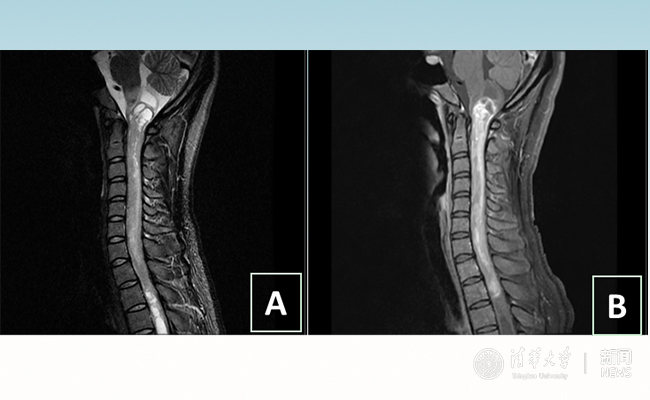

术前影像:图A示肿瘤两端囊变,延髓受累严重;图B示肿瘤强化明显,血供丰富。